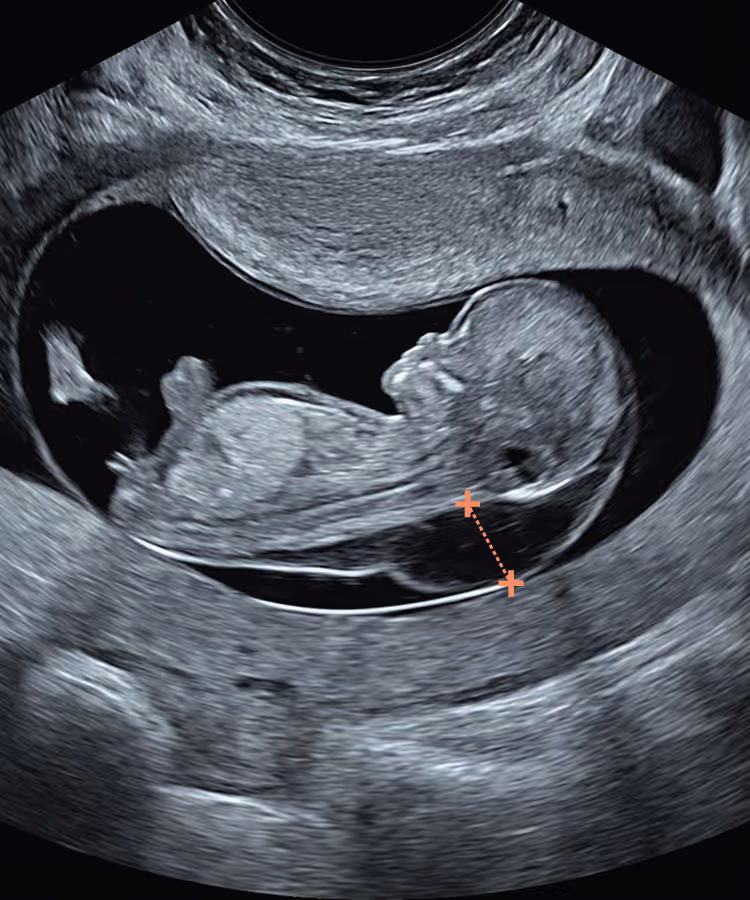

Midline Section: Full CRL view showing head and trunk in mid-sagittal section. The fetus may be face-up or back-up, as long as all mid-sagittal criteria are met.

Visualise: forehead and echogenic nasal tip, brainstem with typical “Z” shape, 4th ventricle and nuchal region

Skin line must be clearly seen, either separated from or merged with amnion. Spine must be straight.

Magnification: The fetal body should fill >60% of the screen.

Calliper Placement: Callipers should be placed on the inner borders of the nuchal translucency. Measurement must be perpendicular to the skin surface (crossbar orientation).

A second visit is usually arranged once the NIPT results are back, typically around 12–13 weeks. At this stage, a more detailed early anomaly scan is performed, with particular attention to the baby’s heart and other organs, and the findings from both the scan and the NIPT are reviewed together. If the NIPT result is high chance, and/or the fetus has persistent increased NT or structural anomalies, the options for invasive diagnostic testing (CVS or amniocentesis) are then discussed.